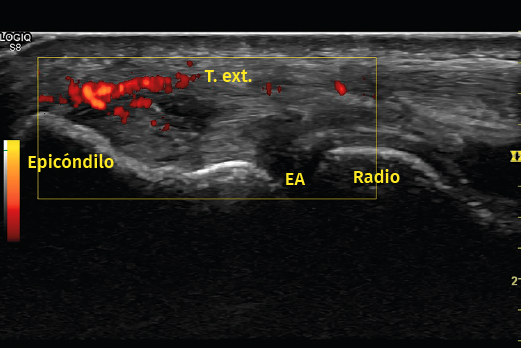

Otro método utilizado es la ecografía, que permite detectar cambios estructurales que afectan a los tendones (engrosamiento, adelgazamiento, áreas degenerativas intrasustancia y desgarros del tendón, por ejemplo), irregularidades óseas o depósitos de calcio(6)(Figura 6). Además, la exploración con Doppler color permite valorar la presencia de neovascularización (Figura 7). La ausencia de este hallazgo o de cambios en la estructura del tendón en las pruebas de imagen debe hacer dudar sobre el diagnóstico de tendinopatía lateral del codo(15). Tiene la ventaja de poder relacionar los síntomas del paciente con los hallazgos ecográficos en tiempo real pero, por otro lado, es operador-dependiente(12). Los estudios demuestran que esta prueba presenta una alta sensibilidad (72-88%), pero una baja especificidad (36-48,5%)(16).

Figura 7. En otra imagen del mismo paciente, al aplicar el Doppler potencia se aprecia un aumento de la vascularización. Imagen cedida por el Dr. Fernando Jiménez Díaz.